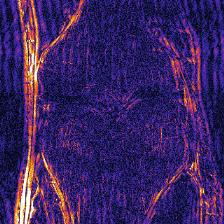

Recently, deep neural networks have greatly advanced undersampled Magnetic Resonance Image (MRI) reconstruction, wherein most studies follow the one-anatomy-one-network fashion, i.e., each expert network is trained and evaluated for a specific anatomy. Apart from inefficiency in training multiple independent models, such convention ignores the shared de-aliasing knowledge across various anatomies which can benefit each other. To explore the shared knowledge, one naive way is to combine all the data from various anatomies to train an all-round network. Unfortunately, despite the existence of the shared de-aliasing knowledge, we reveal that the exclusive knowledge across different anatomies can deteriorate specific reconstruction targets, yielding overall performance degradation. Observing this, in this study, we present a novel deep MRI reconstruction framework with both anatomy-shared and anatomy-specific parameterized learners, aiming to "seek common ground while reserving differences" across different anatomies.Particularly, the primary anatomy-shared learners are exposed to different anatomies to model flourishing shared knowledge, while the efficient anatomy-specific learners are trained with their target anatomy for exclusive knowledge. Four different implementations of anatomy-specific learners are presented and explored on the top of our framework in two MRI reconstruction networks. Comprehensive experiments on brain, knee and cardiac MRI datasets demonstrate that three of these learners are able to enhance reconstruction performance via multiple anatomy collaborative learning.

翻译:最近,深心神经网络大大推进了未经充分取样的磁共振成像(MRI)重建,其中大多数研究都遵循单一解剖一个网络的方式,即每个专家网络都经过特定解剖学的培训和评价。除了在培训多种独立模型方面效率低下之外,这种公约忽视了不同解剖学中共享的、可相互受益的解析知识。为了探索共享知识,一种天真的方法是将各解剖学家的所有数据结合起来,以训练一个全方位网络。不幸的是,尽管存在共享的解析知识,但我们发现,不同解剖学的独家知识可以恶化具体的重建目标,导致总体性能退化。在这项研究中,我们提出了一个新型的深度解剖重建框架,既有解剖学共享知识,又具有具体的解剖学参数,目的是“寻找共同的土壤,同时保留不同解剖学家之间的差异。此外,主要的解剖学学习者将接触不同的解剖学数据,通过多种解剖学重建的模型,并用不同的解剖学研究者将数据展示出一个全方位基础。